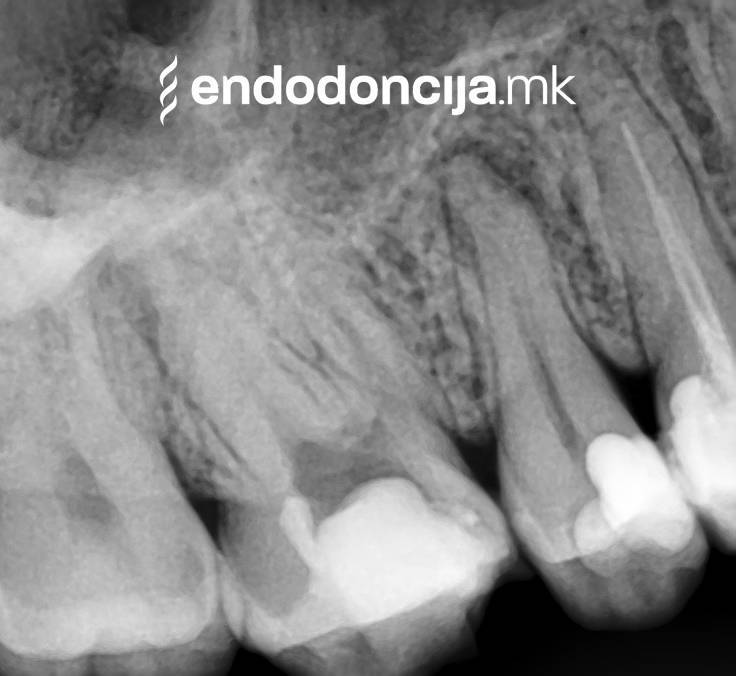

Σε περίπτωση ανανέωσης της θεραπείας του ριζικού καναλιού (αναθεώρηση) παλιά γεμίσματα ρίζας που δεν ήταν επιτυχημένα και ως εκ τούτου ήταν η αιτία φλεγμονών και πόνου, μπορούν να αφαιρεθούν και να ανανεωθούν εξειδικευμένα. Αυτή η θεραπεία εξαλείφει τις φλεγμονές στην περιοχή της ρίζας και καθίσταται δυνατή η πλήρης ανάρρωση.

Κατά τη διάρκεια προηγούμενων θεραπειών, το δόντι μπορεί όχι μόνο να έχει αποδυναμωθεί από τη μηχανική επεξεργασία του ριζικού σωλήνα αλλά και από τη στερέωση και την αγκύρωση ενός ρίζα. Όταν αναθεωρείται η επεξεργασία ενός ριζικού καναλιού, αυτοί οι πείροι πρέπει να αφαιρούνται όσο το δυνατόν πιο προσεκτικά για να διατηρούν σημαντική ουσία των δοντιών.